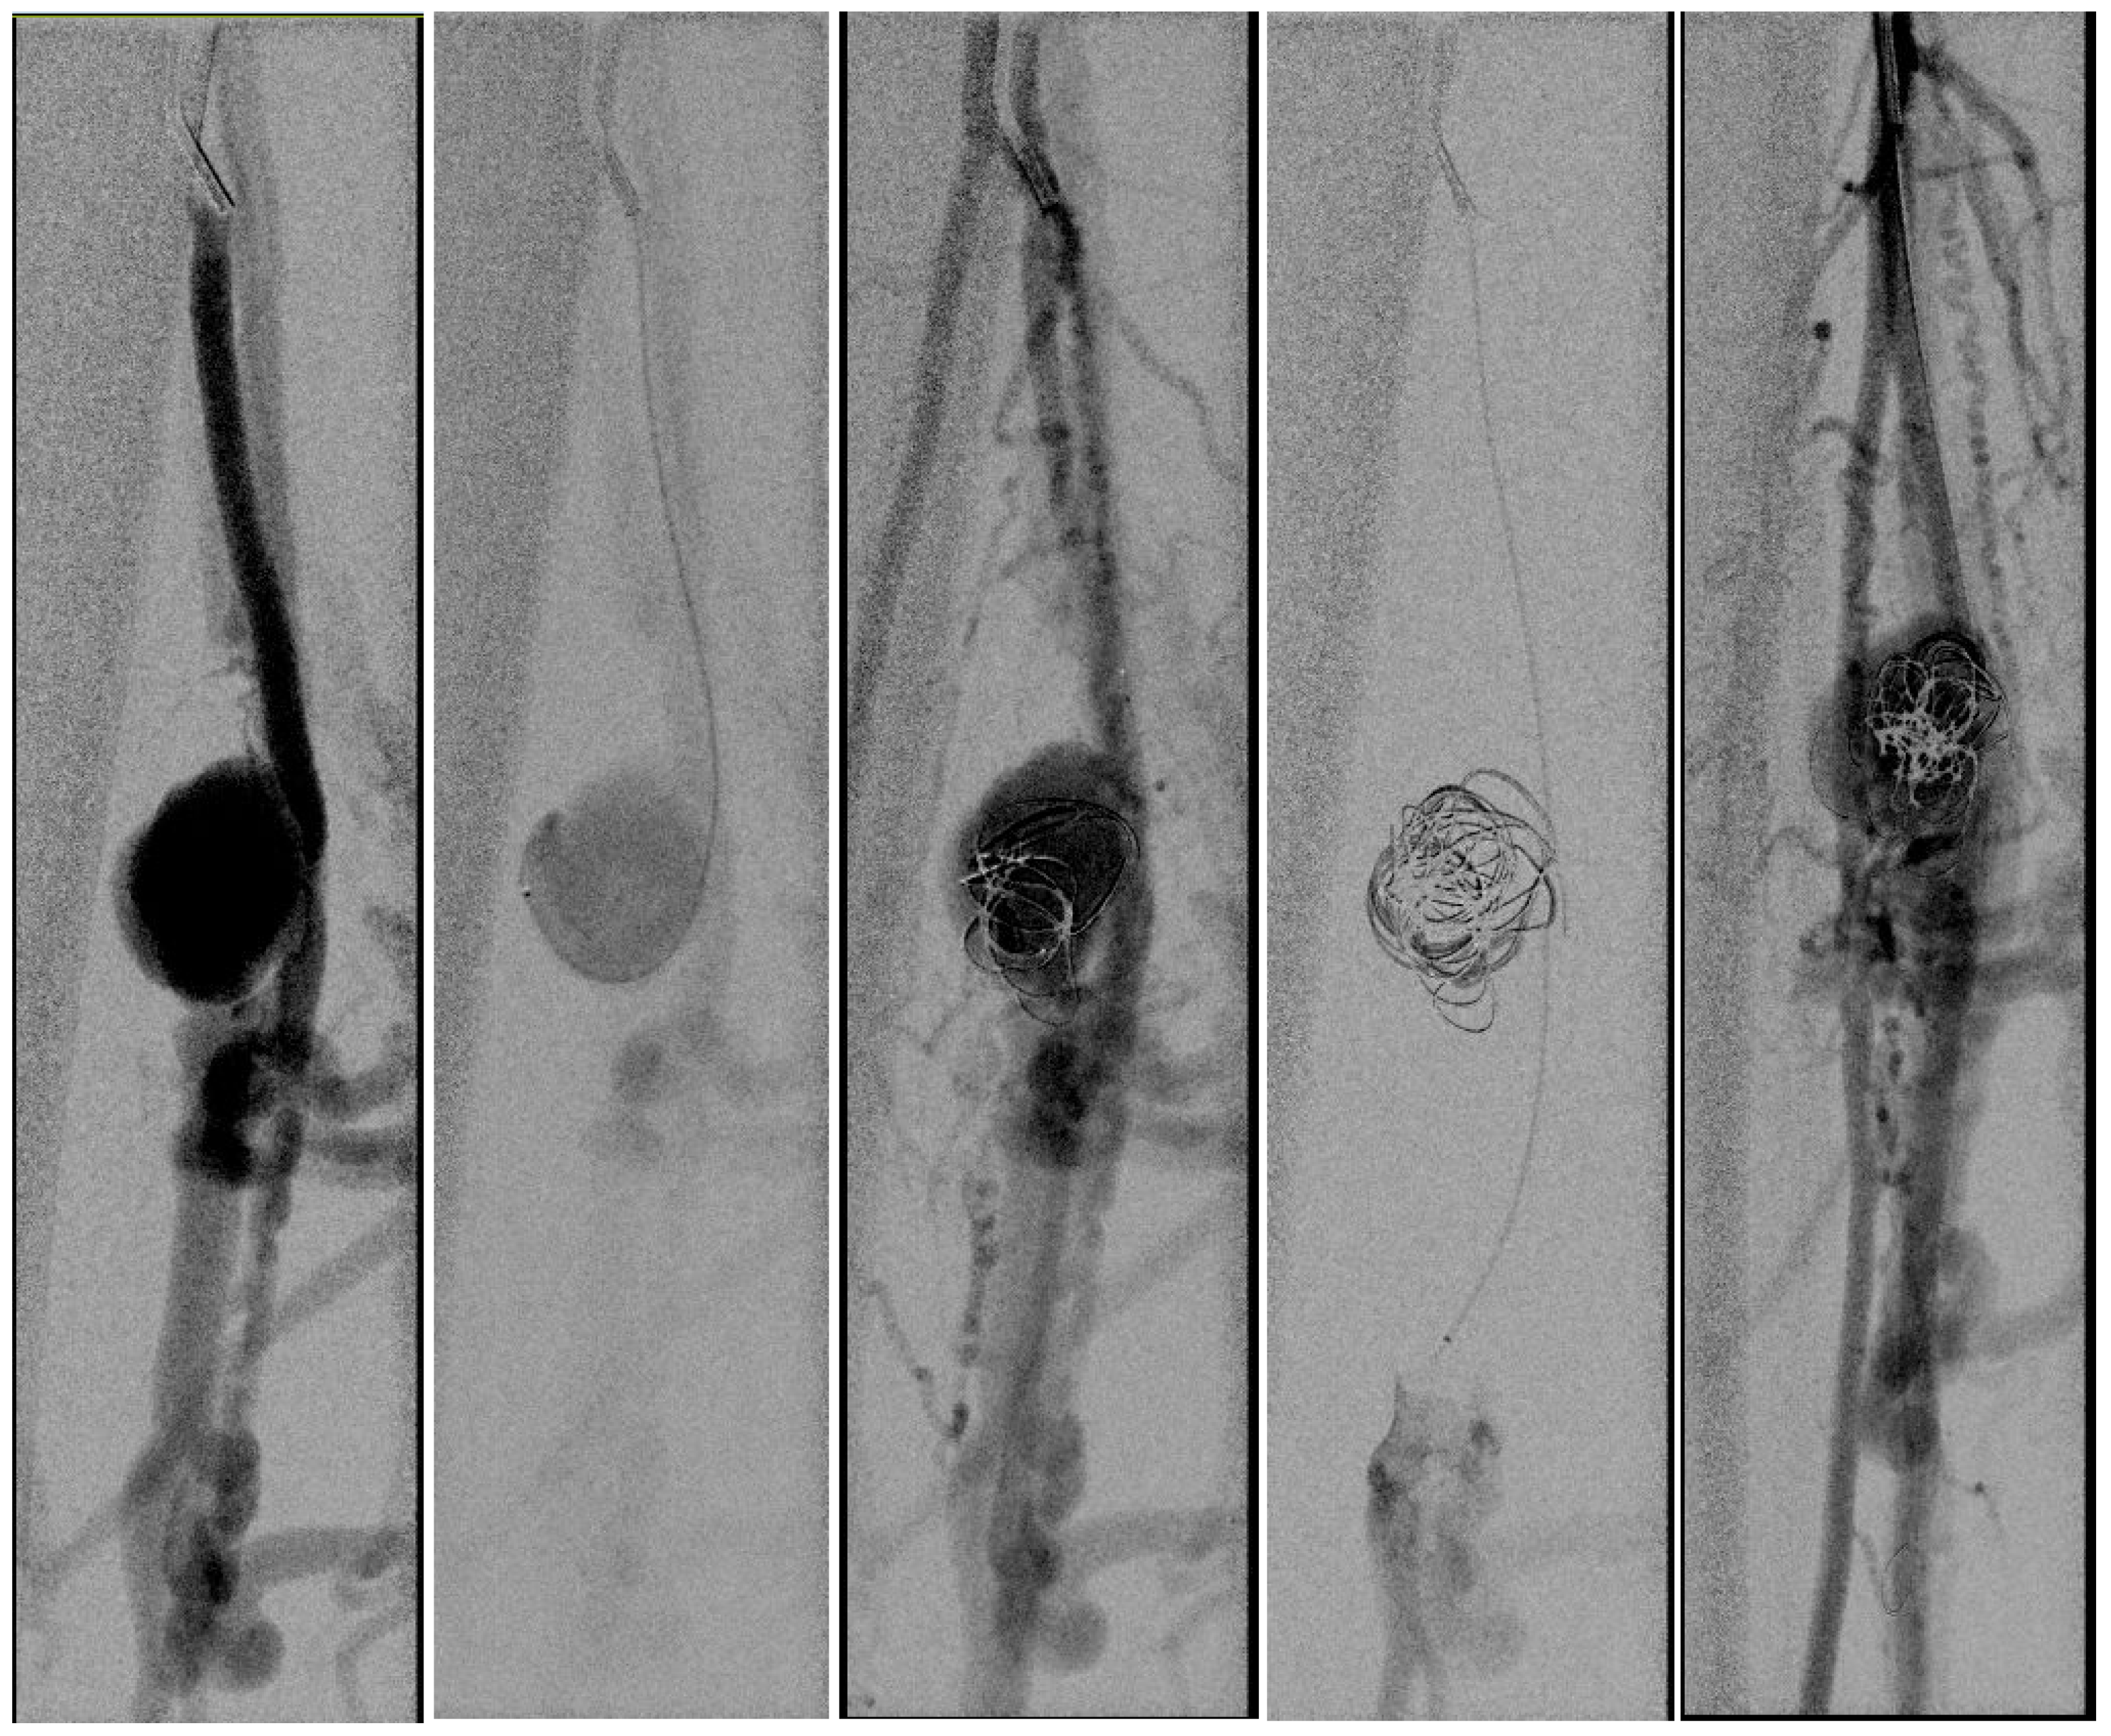

In light of a symptomatic aneurysm, treatment was offered to the patient. After discussing the risks of open and endovascular treatment options with the patient, an endovascular approach was opted for. The presence of a large aneurysm with an AV fistula and venous congestion posed an increased risk of significant bleeding complications associated with open surgery. An antegrade femoral access was obtained via a 5F sheath (Terumo, Shibuya-ku, Tokyo, Japan). After obtaining an angiogram, two coils were deployed in the aneurysm sac (Concerto PGLA helical PV-20-50-Helix and Concerto PGLA 3D PV-18-40-3D, Medtronic, Minneapolis, MN, USA), with the aim of causing sac thrombosis and obliterating the flows from multiple AV fistulas. As anticipated, this did not lead to complete occlusion of the aneurysm and AV fistula. A retrograde pedal access was obtained, and cannulation of the PTA was successfully performed with a V14 guidewire (Boston Scientific, Marlborough, MA, USA) (Figure 2 and Figure 3). After obtaining guidewire access, the aneurysm was excluded with a stent graft (Viabahn Endoprosthesis 5 mm × 50 mm, WL Gore, Flagstaff, AZ, USA). Immediately after the procedure, angiography control visualized complete exclusion of the pseudoaneurysm, occlusion of the sac, and absence of any AVF (Figure 4). Postoperatively, the patient reported pain reduction. Both pedal pulses were palpable. Postoperative antithrombotic therapy included aspirin 100 mg and clopidogrel 75 mg daily for 6 months. Additionally, Class 2 compression stockings were recommended for 1 month. After 18 months of follow-up, the patient was free of symptoms, and the stent graft was patent.

Figure 2.

(Left) to (right). An angiogram was obtained, and the aneurysm sack was coiled. Multiple attempts to cannulate the distal posterior tibial artery failed (A microcatheter is in the crural vein). After coiling the aneurysm sack, the AV fistula was still patent.

Figure 3.

(Left) to (right). Retrograde pedal access was obtained and cannulation was successful with a V14 Guidewire.